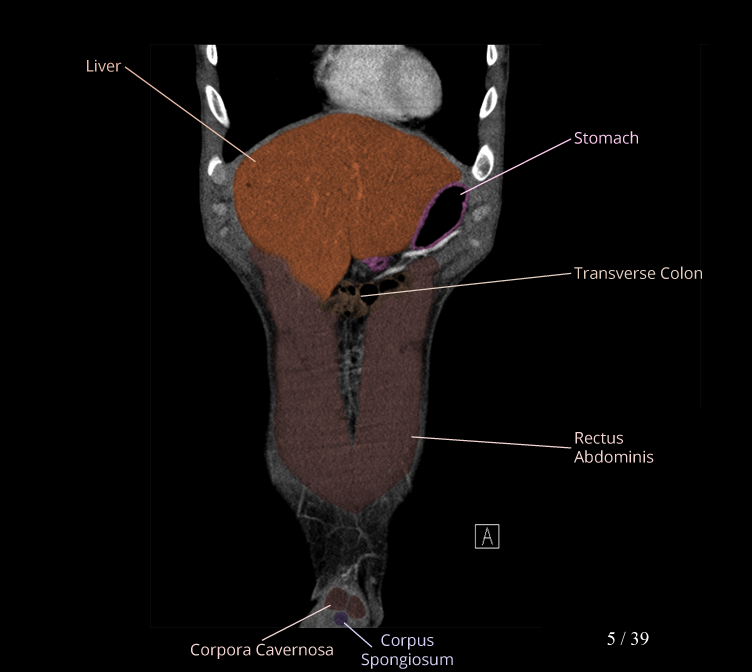

Body

Covers abdominal CT anatomy.